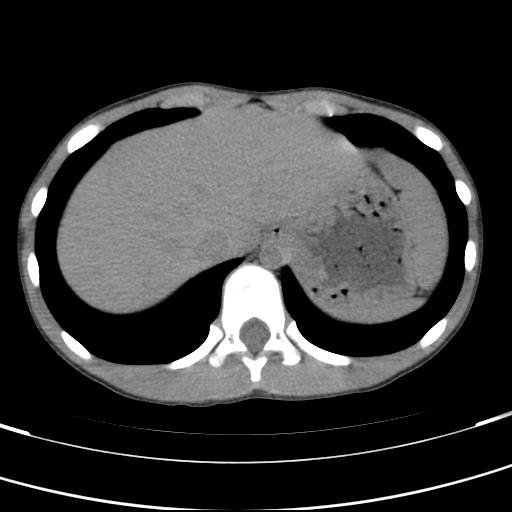

标题: PED3157:左肾缺如,请教脾脏的改变?、、

男孩,9岁。胃部不适。

脾脏位于左侧,但数个脾脏呈分离状态,左肾缺如,右肾代偿肥大。考虑多脾综合征。

脾脏变异,左肾未见,游走、异位、发育不全都要可能,增强或ivp造影。